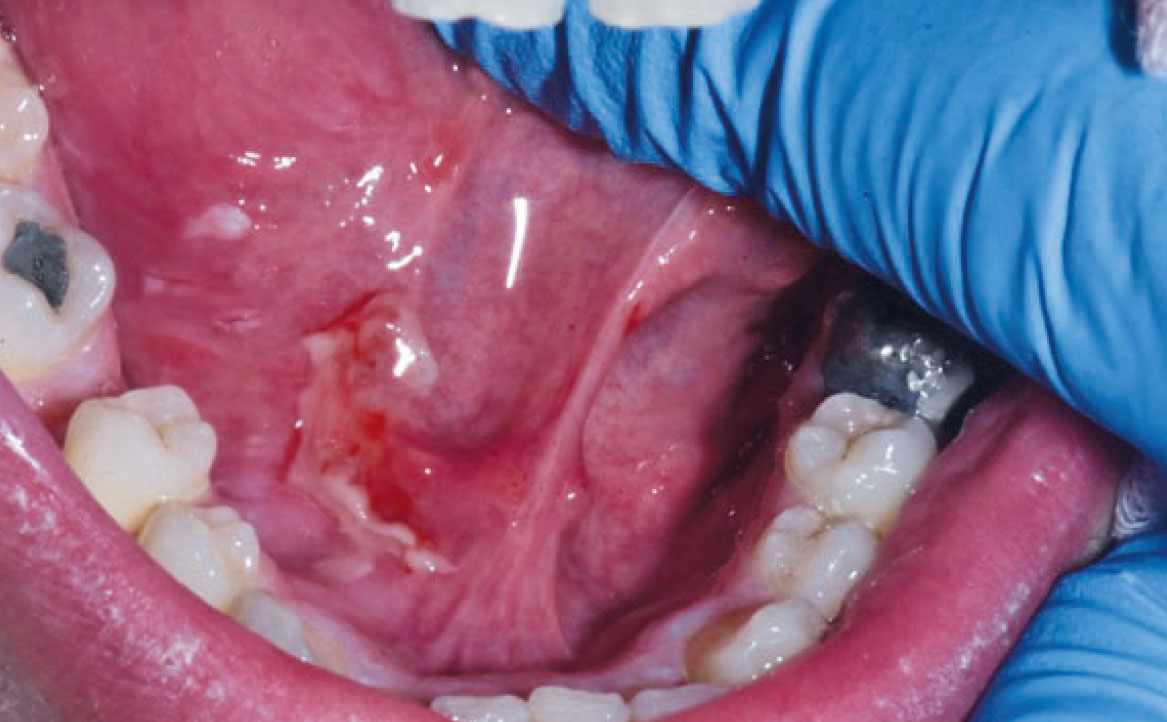

Le patologie vescicole-bollose rappresentano un gruppo di condizioni caratterizzate dalla formazione di vescicole e bolle sulla mucosa orale e sulla cute. Tra queste, il pemfigo volgare è una patologia cronica di natura autoimmune che coinvolge frequentemente la mucosa orale. Le lesioni bollose del pemfigo volgare hanno la tendenza a rompersi facilmente, causando ulcere dolorose. Alcuni farmaci possono indurre lesioni orali clinicamente e istologicamente simili al pemfigo, producendo autoanticorpi diretti contro le molecole desmosomiali e causando acantolisi cheratinocitaria (21). Tra i farmaci più associati a questa condizione vi sono la penicillamina, la rifampicina, il diclofenac e alcuni ACE-inibitori. Inoltre, anche i FANS come il diclofenac, l’ibuprofene e il piroxicam, il fenobarbital, la fenilbutazone, il propranololo e l’eroina possono provocare lesioni simili al pemfigo (fig. 5) (22).